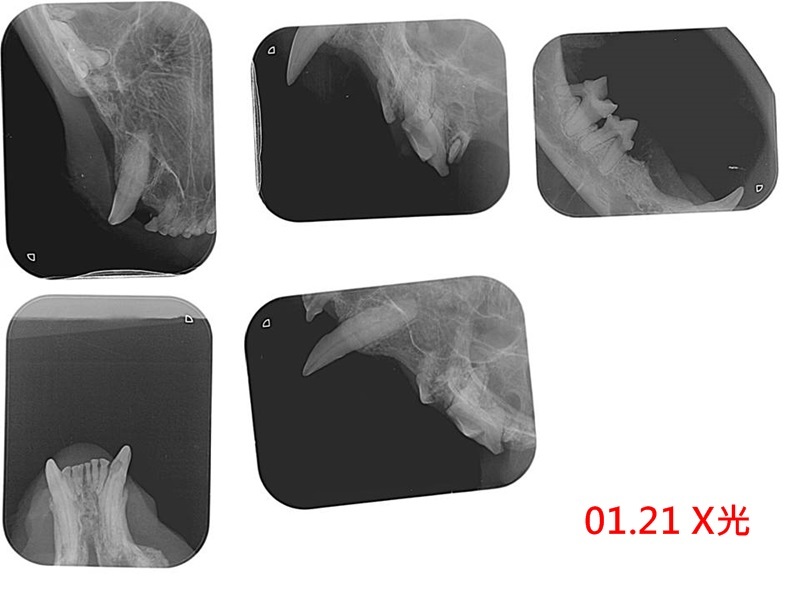

因此在1月21日進行牙周手術將後方全數牙齒、及前方軟組織已潰爛的一顆犬牙拔除,

本筆醫助為旺寶於1月15日至1月28日間至沐恩醫院的看診費用,

包含牙周手術、X光、血檢、口服藥,

二、手術過程

後面的牙齒全數拔除,前面其中一根犬齒,因為軟組織已經潰爛,一併拔除,傷口有縫線,要注意飲食。

另外,牙周手術之後口腔內還有些紅腫的部位,因為擔心有口炎問題,所以下周回診時再看看口腔狀況。